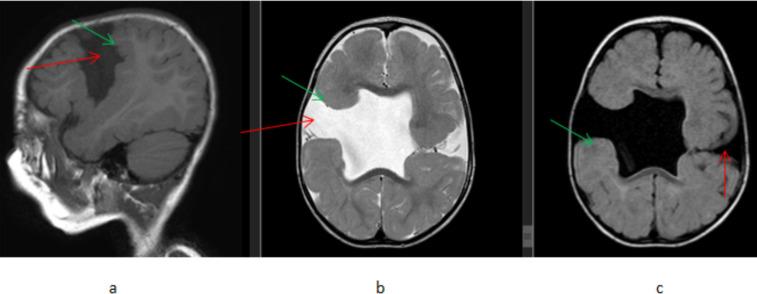

A total of 164 patients were included in this study of which 95(57.9%) were male and 69(42.1%) female patients were seen. A total of 120 patients (73.2%) showed abnormal brain MRI studies. Previous neurovascular insults were the most common abnormalities seen in 75(45.7%) patients followed by imaging findings of congenital and developmental abnormalities seen in 20(12.2%) patients.

本研究共纳入 164 例患者,其中男性 95 例(57.9%),女性 69 例(42.1%)。共有 120 例(73.2%)患者的脑部 MRI 检查结果异常。最常见的异常是既往神经血管损伤,见于 75 例(45.7%)患者,其次是先天性和发育性异常的影像学表现,见于 20 例(12.2%)患者。